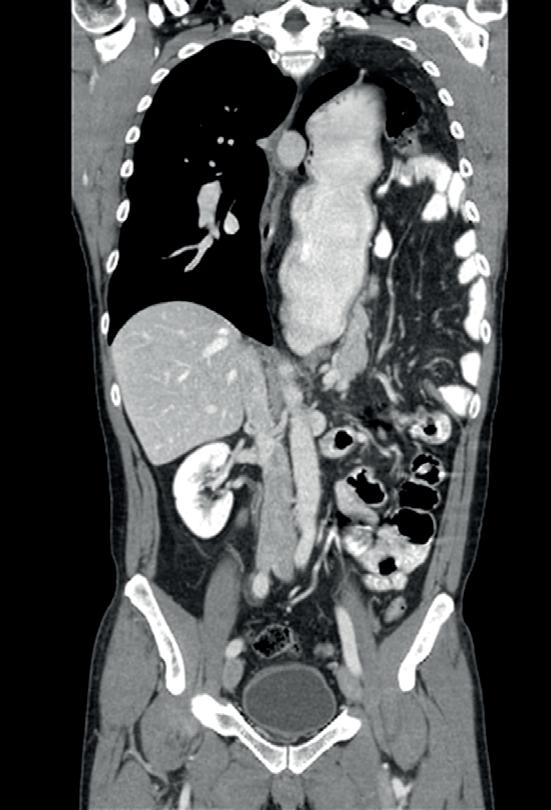

Morgagni hernier utgjør 2% av alle medfødte diafragmahernier (figur 3). Tilstanden skyldes en fremre retrosternal eller parasternal defekt i diafragma. Morgagnihernier kan forbli asymptomatiske og gjennomsnittsalderen ved diagnosetidspunktet er 42 år. En forklaring på sen debut av symptomer er at brokksekken øker i løpet av livet på grunn av høyere trykk i bukhulen enn i thorax.

FIGUR 3: CT-bilde av en pasient med et Morgagni hernie hvor tarm og ventrikkel har herniert opp i høyre torakshule. FIGUR 1: Oversikt over medfødte diafragmahernier. IVC = Inferior Vena Cava. FIGUR 2: CT-bilde av en pasient med et Bochdalek hernie hvor tynntarm, kolon og ventrikkel har herniert opp i venstre thorakshule og fyller store deler av denne.